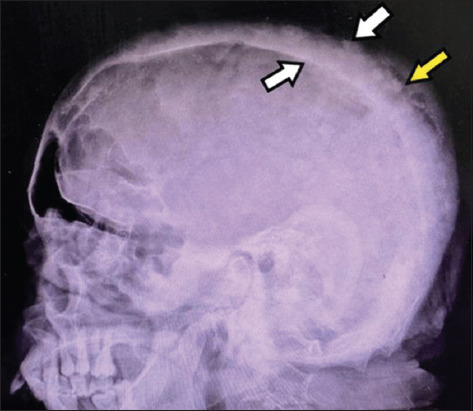

Background and aim: Paget's disease of the bone refers to a chronic cumulative disorder characterized by enhanced osteoclastic function followed by a secondary surge in osteoblastic activity. The condition can manifest as a polyostotic or monostotic bone disease with most patients having an asymptomatic presentation, although some may complain of pain localized to the affected bone while others express symptoms of nerve compression. A pagetic bone is predisposed to develop pathological fractures, bony deformities, and a rare yet detrimental transformation into osteosarcoma. Detection is often accidental when performing radiographic tests for other indications or when elevated blood levels of alkaline phosphatase (ALP) are detected. Treatment with third-generation bisphosphonates is helpful in preventing further bone resorption and, additionally, reduces bony pains that are believed to be caused by excessive metabolic activity. Here, we present a case of a middle-aged asymptomatic female with elevated serum ALP levels up to 1537 IU/L (reference range 40-150 U/L) during her pre-operative evaluation for elective cholecystectomy.99m Tc-methylene diphosphonate bone scintigraphy revealed diffuse uptake in the skull and, hence, was diagnosed as a case of isolated Paget's disease of the skull.

Relevance for patients: The rarity of this disease in Southeast-Asians, its uncontrived detection, and the isolated skull involvement, imparts high clinical relevance on this case. Early detection and management of this disease can help prevent the development of life-threatening complications in affected patients, hence decreasing the morbidity.